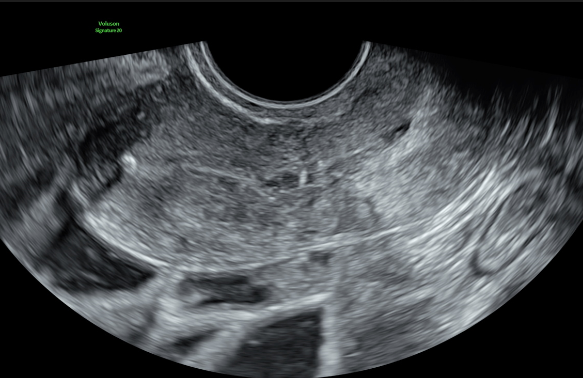

About Transvaginal Ultrasound

Transvaginal ultrasound is only performed with your consent. This approach allows a much better, high-resolution, detailed assessment. A sterile, narrow transducer is used. Please let us know if you are concerned about the procedure, and your sonographer will discuss this with you before starting your scan.